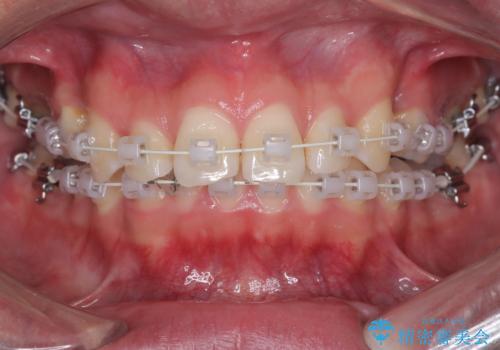

叢生(歯のデコボコ)の量が多く、加えてディープバイト(過蓋咬合)や重度の捻転も認められたため、リンガルアーチやマイクロインプラントなどの補助装置を併用し、治療を進めました。

治療途中では咬み合わせの改善を目的としてバイトアップを行い、歯の捻転や叢生を改善しつつ、機能的に安定した咬合を獲得しています。